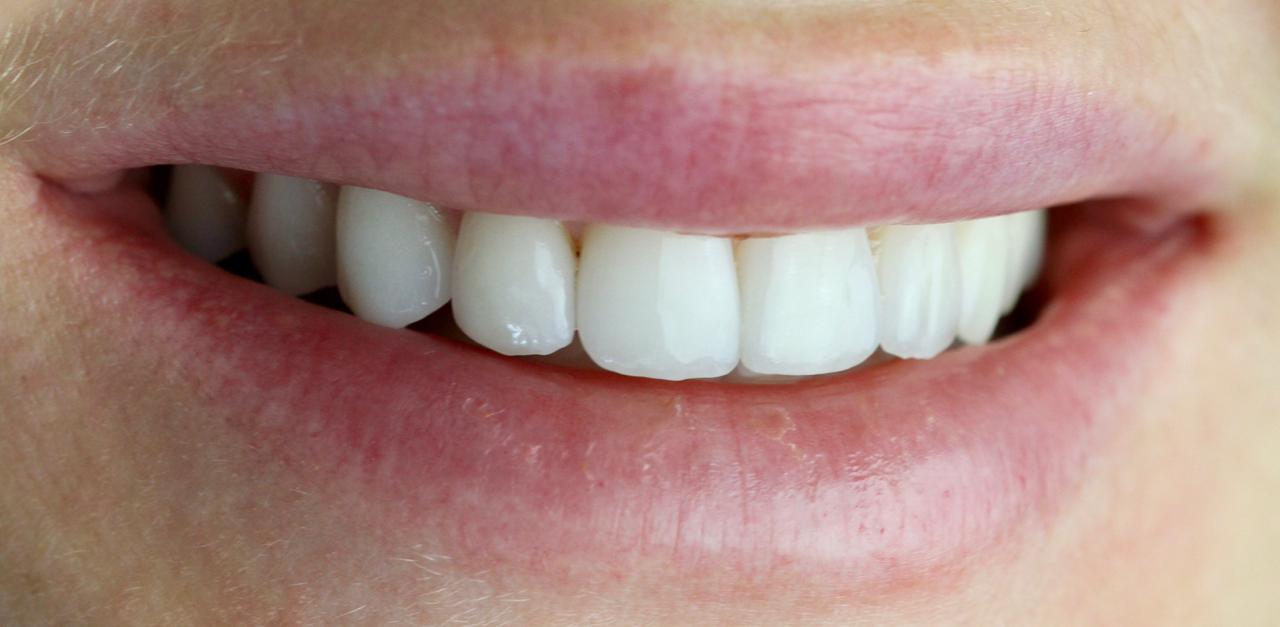

Снова виниры

Замена старых виниров темного цвета на более светлые по причине оголения шейки зуба.

Виниры цвета BLEACH

Установлены керамические виниры на верхнюю челюсть по эстетическим требованиям.